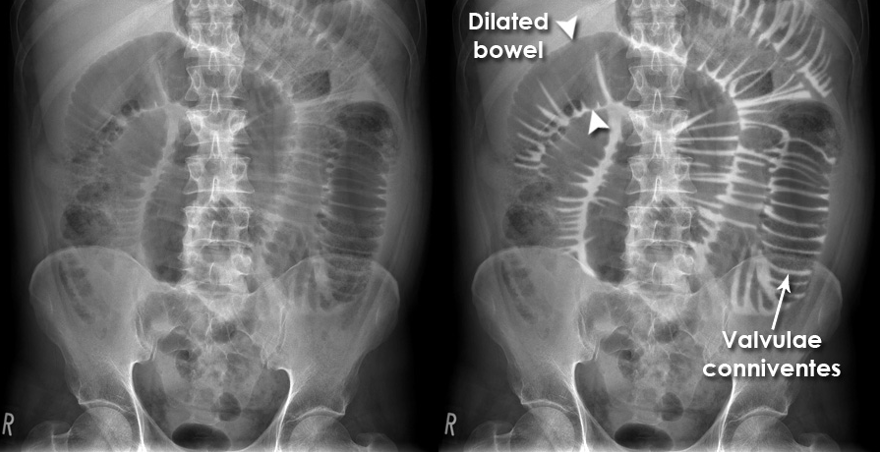

Answer: D) Sigmoid volvulus

Explanation: A coffee bean sign is shown which is an indication of a sigmoid volvulus, which is a condition where the sigmoid colon twists on its mesentery, causing obstruction.

C) is incorrect because caecal volvulus presents with the kidney bean sign.

E) is incorrect because small bowel obstruction shows dilatation of more than 3 cm and is characterised by the presence of plicae circularis/valvulae conniventes.